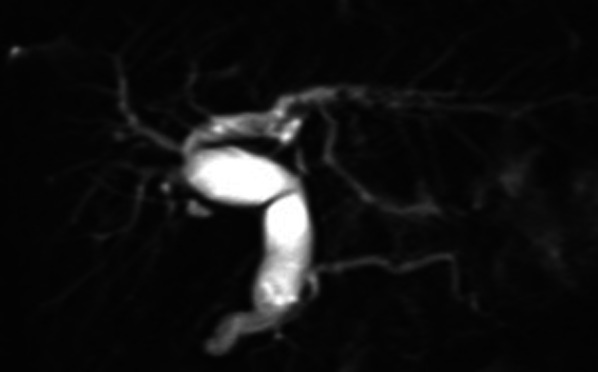

A 9-year-old girl was referred to our hospital for further examination regarding dilatation of the common bile duct, which was found by abdominal ultrasonography performed for the evaluation of elevated liver enzyme levels. Magnetic resonance cholangiopancreatography (MRCP) revealed dilated bile ducts from the left and right intrahepatic bile ducts to the common bile duct, and the patient was diagnosed with Todani type IV-A CBD (Fig. 1). The gallbladder was not detectable by abdominal ultrasonography, computerized tomography or MRCP; therefore, we suspected gallbladder agenesis preoperatively. The patient underwent laparoscopic excision of the extrahepatic bile duct to treat the CBD. Initial laparoscopic exploration did not reveal a gallbladder or cystic duct on the liver undersurface. Therefore, we considered gallbladder agenesis based on both preoperative imaging and intraoperative findings. Intraoperative cholangiography was performed by direct puncture of the common bile duct, and it did not show the gallbladder and bile duct (Fig. 2). However, during dissection of the hepatic hilum, we detected a cystic structure on the ventral side of the common hepatic duct, slightly to the right, and the presence of a small additional duct that originated from the cystic structure (Fig. 3). The size of the cystic structure was estimated to be 3 cm and the distance between the cystic duct and bifurcation was estimated to be 1.5 cm. A small amount of bile was drained upon incising the small duct. Thus, we diagnosed the cystic structure as an ectopic gallbladder with hypoplasia. After the ectopic gallbladder was removed, an excision of the extrahepatic bile duct followed by laparoscopic Roux-en-Y hepaticojejunostomy was completed without any complications. Postoperative histopathological evaluations of the resected specimen revealed Rokitansky–Aschoff sinuses in the resected cystic lesion (Fig. 4). Findings from the pathological investigations confirmed the diagnosis of an ectopic gallbladder. The patient’s postoperative course was uneventful, and she was discharged on the ninth postoperative day. She recovered without any hepatobiliary complication 10 months after the operation.